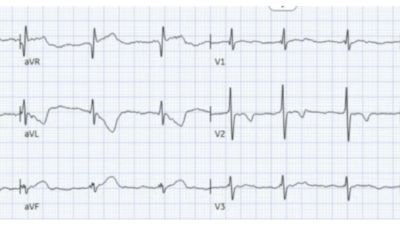

Here is her triage ECG:

Smith: This is classic for pulmonary embolism (PE). There are 2 key points to making this diagnosis on the ECG:

- 1) There is T-wave inversion which you might think is due to Wellens’ waves, but the patient has active symptoms, so it is not Wellens’ sydrome

- 2) The T-wave inversion in V1-V4 is accompanied by T-wave inversion in lead III. This is very specific for PE vs. ACS.

Also, and much less teachable: the T-waves just don’t look right for ACS.

We’ve reviewed the ECG clues to acute PE in those more than 20 links that Dr. Meyers’ lists above. I found today’s initial ECG interesting — in that most of the time, the ECG diagnosis of acute PE is highlighted by more than just a couple of the ECG Findings that I list below in Figure-2.

- For example, in today’s initial ECG (that I’ve reproduced and labeled in Figure-1) — there is no sinus tachycardia — and no right axis, RAA, incomplete or complete RBBB, tall R in lead V1, persistent precordial S waves, ST elevation in lead aVR or AFib.

That said — the following are present in today’s case:

- A suggestive History (shortness of breath with chest pain as the chief complaint).

- An S1Q3T3.

- Deep symmetric T wave inversion in the anterior chest leads (BLUE arrows in Figure-1) — that occurs in association with T wave inversion suggesting RV “strain” is present not only in the anterior chest leads, but also in inferior leads III and aVF.

PEARL (as per Drs. Meyers and Smith): When there is T wave inversion in the chest leads — IF there is T wave inversion in both lead V1 and lead III ==> Think acute PE (and not ACS! ).

- By itself — the S1Q3T3 sign seen in Figure-1 would not be specific for acute PE (ie, I have seen this sign in healthy individuals with no acute pulmonary pathology). However, in the presence of a suggestive history and the extensive T wave inversion seen in today’s case — the S1Q3T3 strongly supports the diagnosis of acute PE.

- T wave inversion as diffuse as is seen in Figure-1 — most often suggests a sizeable PE (which makes it all the more surprising that there is no tachycardia and a lack of more of those ECG findings that are listed in Figure-2).

- Finally — the Q in lead III — the ST coving with slight ST elevation + T wave inversion in leads III and aVF — and the ST segment straightening in lead aVL — might lead one to misinterpret today’s ECG as indicative of ACS. IF tempted to do so — it is worth rereading the above PEARL!

Figure-1: I’ve labeled the initial ECG in today’s case.